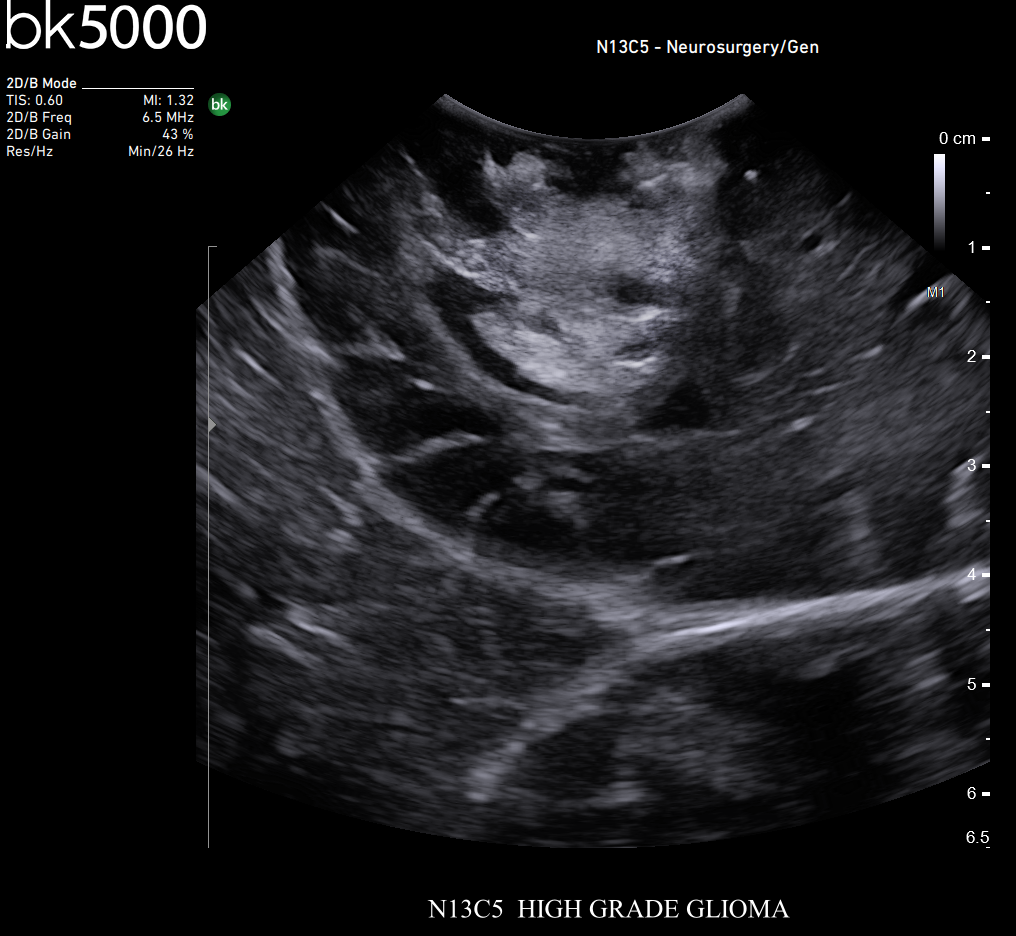

Ultrasound can improve neurosurgical procedures by helping you navigate and identify lesions and anatomical structures in real-time. This is particularly important as the data obtained from a preoperative CT or MRI scan can be outdated at the time of surgery. The bk5000 neurosurgical system provides the highest quality images that allow you to clearly see the margins of a lesion and to determine the best course of action. Using advanced graphics processing technology, this powerful system provides immediate, auto-optimized images that allow you to see the information you need, faster.

Transducers designed for Neurosurgery

The specialized, high-resolution, sterilizable neurosurgery transducers enable you to obtain detailed images of the brain and spinal cord. They have a convenient Smart™ button that lets you activate the transducer, then freeze, store or print the images at the press of a button. Disposable, easy-to-use needle guides assist with targeting lesions.